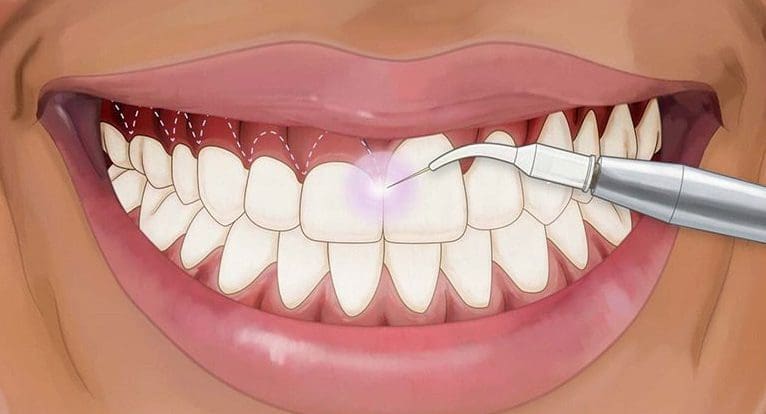

حشوات الأسنان بالليزر

في الآونة الأخيرة، اجتاحت تقنية الليزر مجال طب الأسنان، وخاصة في الجراحة التجميلية، دعونا نتعرف على حشوات الليزر معًا.

أولاً، يساعد الليزر في اكتشاف الفجوات في الأسنان ويوضح الأماكن التي تحتاج إلى حشوات. كما يستخدم الليزر للقضاء على جميع أنواع البكتيريا في الحشوات وبين الأسنان وهي عملية لا تتطلب أي تخدير. يساعد الليزر أيضًا في القضاء على الحساسيات للحرارة أو البرودة. من المؤكد، الليزر فعال جدا في تبييض الأسنان وتنظيفها.

مخاطر استخدام الليزر في عمليات الاسنان

ينطوي استخدام الليزر في طب الأسنان على بعض المخاطر البسيطة، وهي:

- لا يمكن استخدامه بعد حشو الأسنان بالملغم

- قد يتسبب بأضرار على مستوى بنية الأسنان

- لا تزال بعض إجراءات الأسنان بالليزر تتطلب التخدير

- لا يكفي وحده أحياناً قبل الحشو

- احتمالية إصابة اللثة